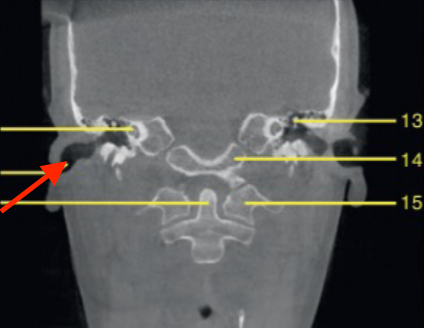

coronal

what plane

posterior of maxillary sinus

where is this slice

mental foramen (at premolar region)

identify the structure

molar region

where is this slice located

mandibular canal/inferior alveolar canal

what is the ARROW pointing to